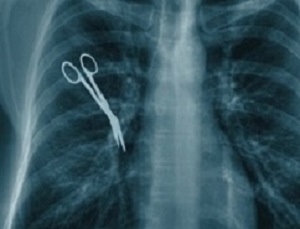

Of the 185 cases in which pay-outs had been made in the past two-and-a-half years‚ seven cases involved blindness caused by negligence, reports The Times. Paraplegia was caused in three cases. In one case‚ a nurse left a cleaning pad inside a mother's womb at a hospital.